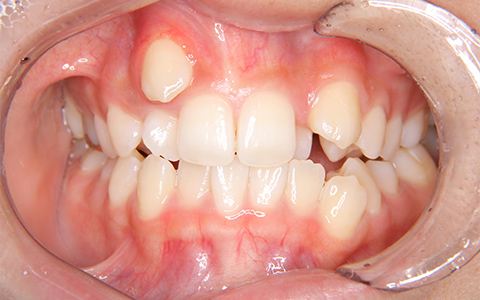

治療前

治療後

施術内容 右上3番の位置が気になるとのことでご来院(16歳)。犬歯の異所萌出、上顎骨の狭窄に対するマルチブラケット装置による抜歯(上顎両側4番を抜歯)治療

治療期間 2年6ヵ月(通院30回)

費用 880,000円

リスク・副作用 歯が動く痛み、歯髄壊死、歯根吸収、歯肉退縮、リテーナーを使用しないことによる後戻り